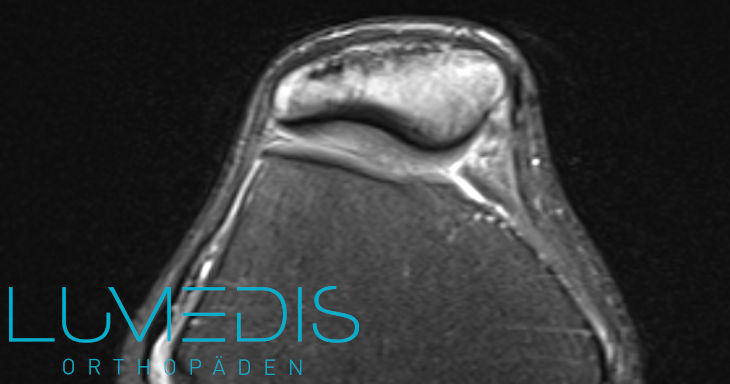

MRT einer Jägerhutpatella

Die Jägerhutpatella ist farbig eingefärbt (rot).

Eine MRT der Kniescheibe kann und sollte dann durchgeführt werden, wenn vorangegangene Untersuchungen keinen Hinweis erbracht haben, die Beschwerden aber weiterhin noch vorhanden sind. Auch wenn man vermutet, dass die Beschwerden von verletzten Sehnen, Muskeln, Menisken oder Bändern verursacht werden, sollte eine MRT Aufnahme des Knies durchgeführt werden. Die strahlungsfreie Schnittbildaufnahme dauert ca. 15 Minuten und kann alle Gewebe des Knies zuverlässig darstellen.

MRT der Kniescheibe (T2) - das Kniegelenk wird horizontal geschnitten (oben ist die Kniescheibe, unten geht es zur Kniekehle)